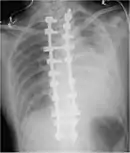

Thoracostomy

Blood in the cavity can be removed by inserting a drain (chest tube) in a procedure called a tube thoracostomy. This procedure is indicated for most causes of hemothorax, but should be avoided in aortic rupture which should be managed with immediate surgery.[30] The thoracostomy tube is usually placed between the ribs in the sixth or seventh intercostal space at the mid-axillary line.[15] It is important to avoid a chest tube becoming obstructed by clotted blood as obstruction prevents adequate drainage of the pleural space. Clotting occurs as the clotting cascade is activated when the blood leaves the blood vessels and comes into contact with the pleural surface, injured lung or chest wall, or the thoracostomy tube. Inadequate drainage may lead to a retained hemothorax, increasing the risk of infection within the pleural space (empyema) or the formation of scar tissue (fibrothorax).[31] Thoracostomy tubes with a diameter of 24–36 F (large-bore tubes) should be used, as these reduce the risk of blood clots obstructing the tube. Manual manipulation of chest tubes (referred to as milking, stripping, or tapping) is commonly performed to maintain an open tube, but no conclusive evidence has demonstrated that this improves drainage.[8] If a chest tube does become obstructed, the tube can be cleared using open or closed techniques.[32] Tubes should be removed as soon as drainage has stopped, as prolonged tube placement increases the risk of empyema.[33][6]